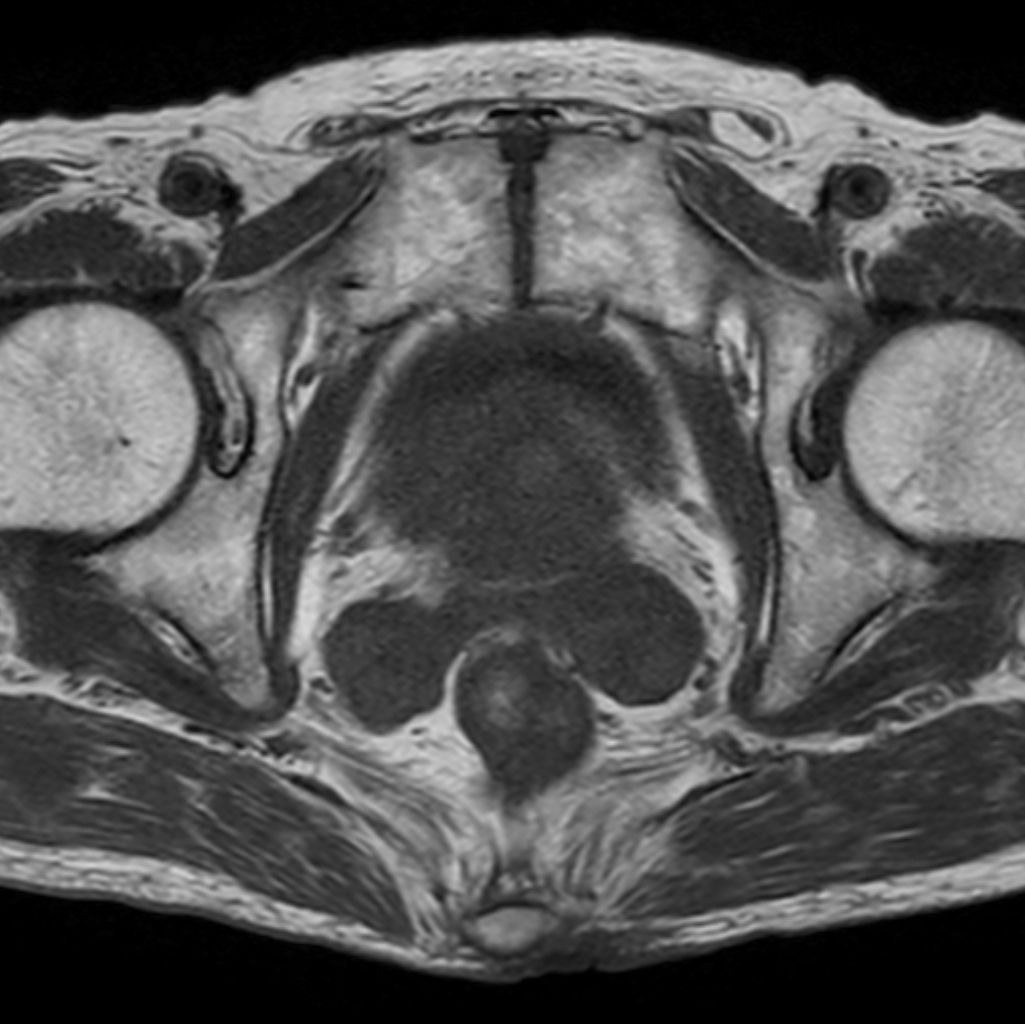

Axial T2w TSE